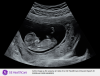

Hej, ja już po prenatalnych, wszystko jest ok 😍

Bobo strasznie szalało, więc było trudno zrobić pomiary, to pewnie przez kawę, którą wypiłam 😁

Nie dało się określić płci, lekarka powiedziała, że ten wyrostek jest w takiej pozycji pośredniej, że nie da się nic powiedzieć konkretnego. W każdym razie odetchnęliśmy z ulgą, jutro idę na badanie krwi, bo kazała mi być na czczo.

O jaki bobuś.. przesłodki. 🙂Mamacita wrote:Hej, ja już po prenatalnych, wszystko jest ok 😍

Mamacita, wow ale piękne dziecko. To już nie jest tyranozaurokrewetka, to w pełni ukształtowane dziecko!